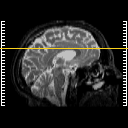

[Home][Help][Clinical] Slice 36

Click on sagittal image to select slice. Click on thin tickmark to change timepoint, or thick tickmark for overlay.